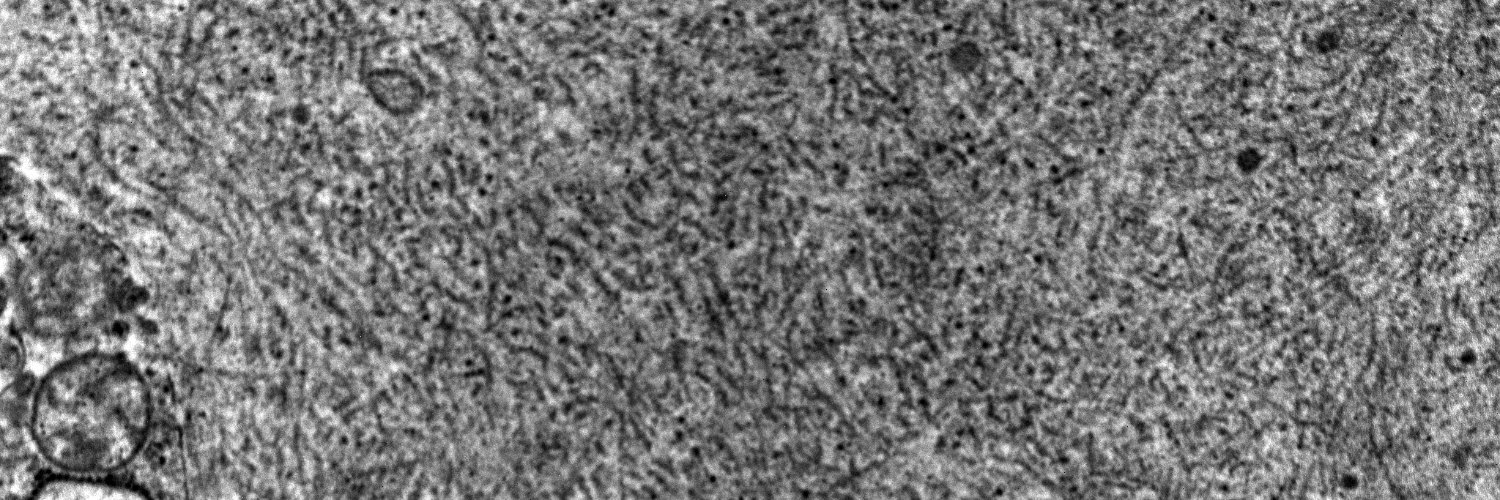

Corticosteroids are the cornerstone of therapy for steroid-sensitive nephrotic syndrome, yet the best dosing strategy remains uncertain. Read this Systematic Review /Meta-analysis of single-dose vs. multi-dose steroid therapy in pediatric NS. #OpenAccess